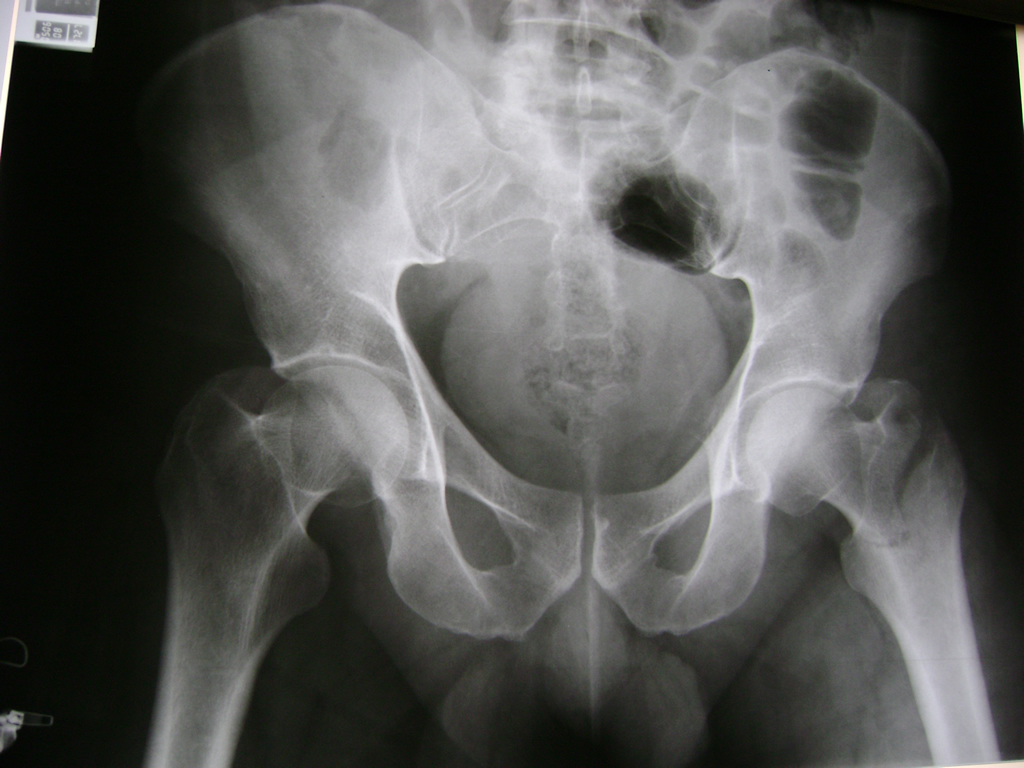

La cirugía de fractura de cadera se realiza para reparar una ruptura en la parte superior del hueso del muslo. Este hueso se denomina fémur.

Es parte de la articulación coxofemoral. Si una fractura de cadera no recibe tratamiento, es posible que deba permanecer en una silla o en la cama.

Esto puede llevar a otros problemas de salud potencialmente mortales, sobre todo si usted es una persona mayor.

A menudo se recomienda la cirugía para reparar la fractura debido a dichos riesgos.